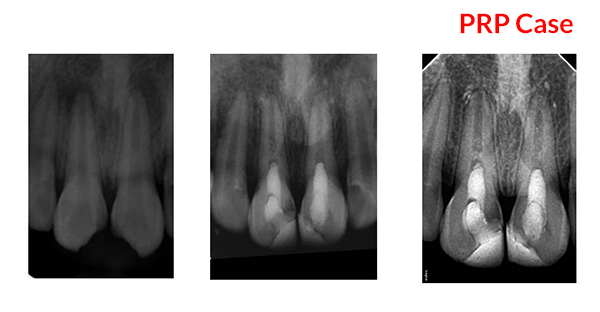

Tanisha Konai -

PRP Mediated REP in 21 with 18 months follow up

Bone healing, Apical PDL formed, Apex Closed, Calcific Bridge formed in 21.

Vitality Positive